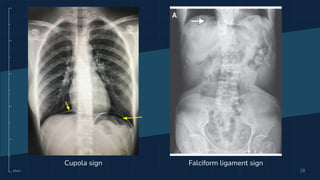

Pneumoperitoneum

➔ Udara bebas intraperitoneum/ekstraluminer

➔ Gambaran radiologi:

◆ Cupola sign → udara di bawah diafragma

◆ Football sign

◆ Rigler sign/ double wall sign

◆ Ligamentum falciforum sign

◆ Umbilical ligament sign/ tanda V terbalik

◆ Urachus sign

Cupola sign Falciform ligament sign